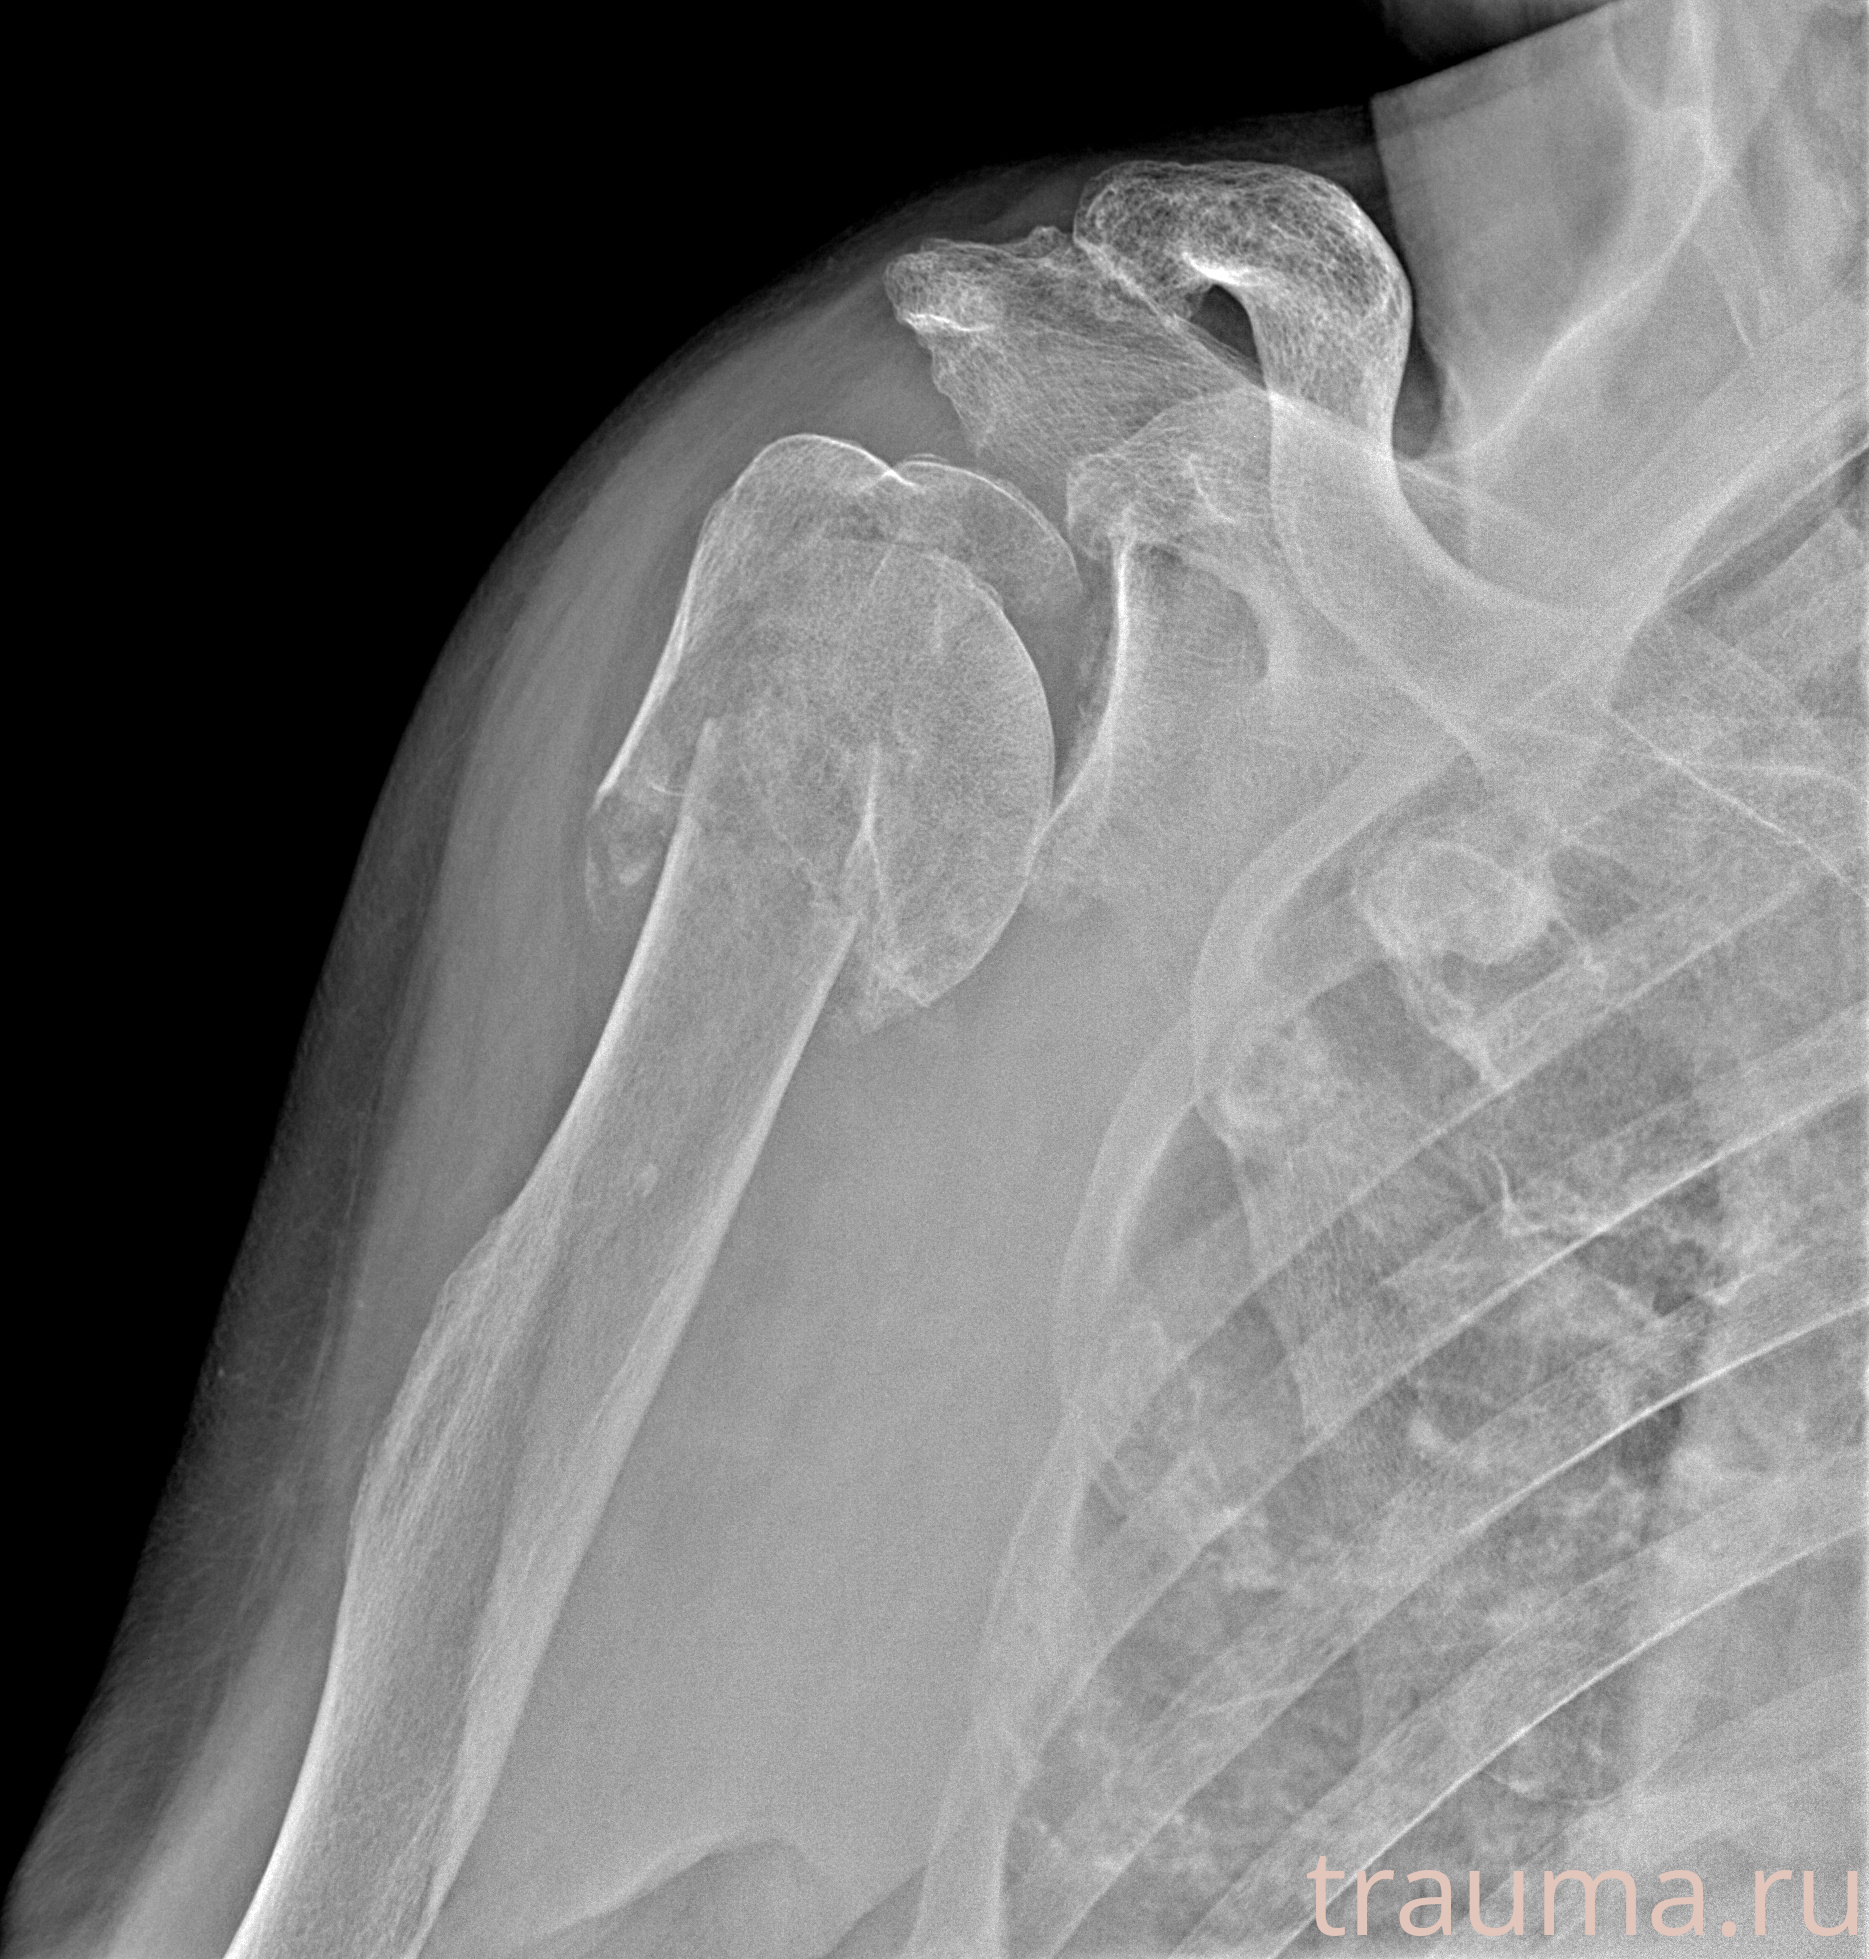

Рентгенограммы

Рентген на дому: по вашему адресу приезжает врач-рентгенолог, травматолог-ортопед с мобильным рентгеновским аппаратом, проводит диагностику травмы или заболевания, делает необходимые рентгенограммы, дает рекомендации по дальнейшему лечению. Получить качественные снимки в домашних условиях возможно благодаря уникальной методике, разработанной МосРентген Центром для института  Склифосовского